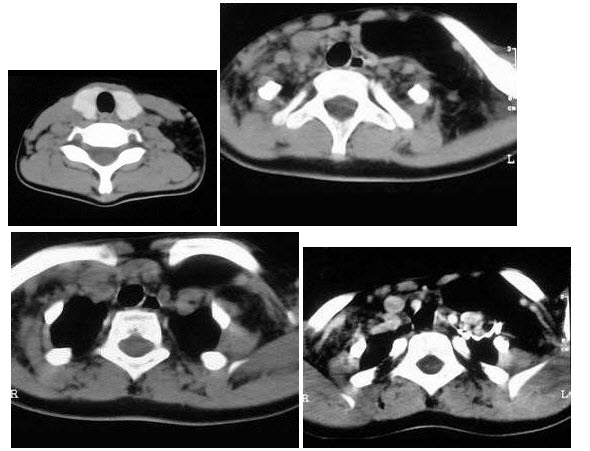

87、多项选择题

该病人突发胸部疼痛,进行性呼吸困难,行X线片检查,提示右下肺病变,急诊CT平扫加增强,如图所示()

A.X线片示右下肺实变影

B.SCT增强扫描示右侧肺动脉主干完全性充盈缺损

C.右肺动脉开口处见不规则软组织密度影

D.考虑为右侧肺动脉(中央性)栓塞

E.考虑为右侧肺癌